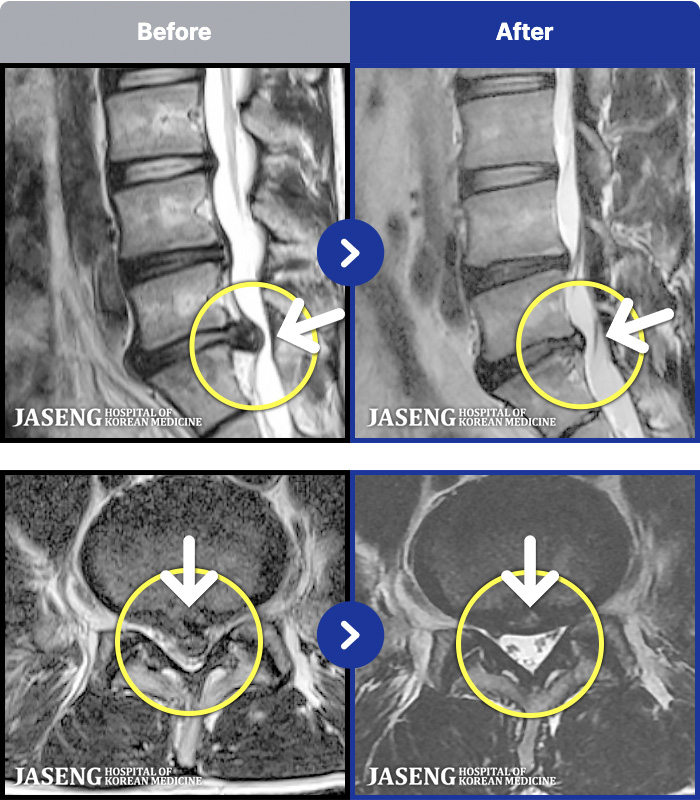

1,286 MRI ũ ʸ Ȯϼ.

[ϻ] 24.07.25~25.08.01